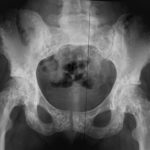

Osteopoikilosis

OSTEOPOIKILOSIS (OSTEOPATHIA CONDENSANS DISSEMINATE; SPOTTED BONES) Autosomal dominant inheritance, with loss of function mutation in…